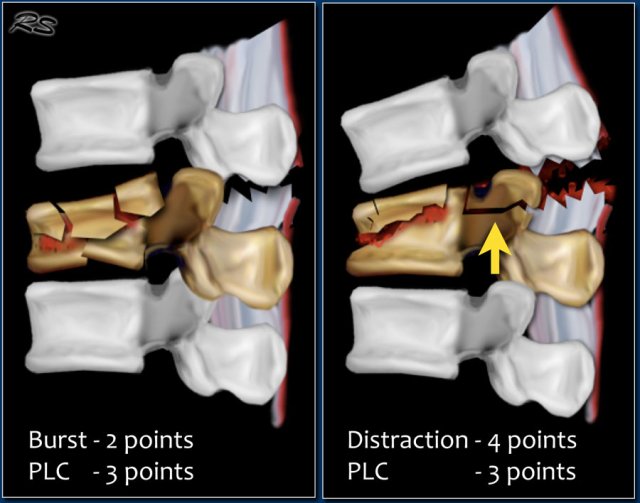

In some cases it can be difficult to decide whether there is a burst fracture with a torn PLC or distraction with a torn PLC and a compression fracture (figure).

You have to decide what you think is the main issue: the collapse of the vertebral body or the distraction.

Since in both cases the TLICS score based on imaging will be high, there is usually an indication for surgical treatment.

In some cases it is difficult to decide whether you are dealing with distraction combined with a compression fracture or with a compression fracture with PLC-injury.

If the distraction is the main feature, then the morphology is distraction, i.e. 4 points.

In these cases the PLC is always involved, resulting in a total of 7 points for the TLICS-score.

If compression is the main feature, then the morphology is burst, i.e. 2 points combined with the PLC injury making a total of 5 points.

In both cases the patient is a surgical candidate.